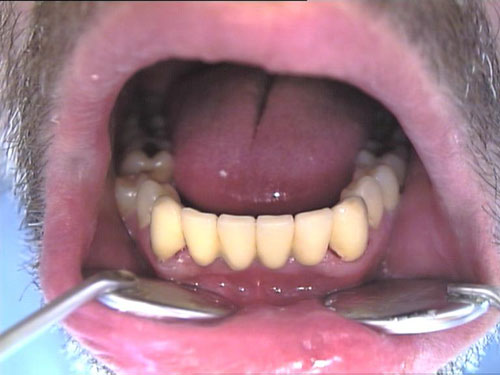

Keramikkrone 1

Keramikkrone 2